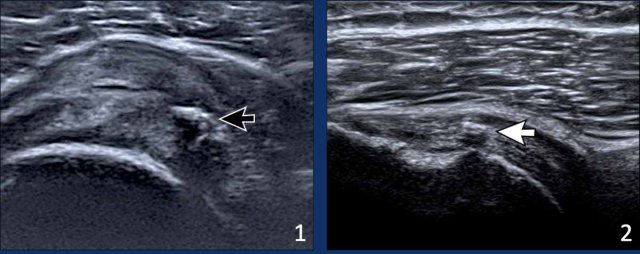

Subscapular tendon

The arm is positioned alongside the trunk, with the elbow flexed at a 90º angle between the arm and forearm.

The forearm is placed in supination and external rotation.

The ultrasound probe is positioned medially to visualize the subscapularis (SSC) tendon as it passes beneath the coracoid process.

Video of normal subscapular movement

During internal and external rotation of the forearm, the whole tendon should be seen sliding under the coracoid (see video).

Impingement is noted when there is incomplete or delayed passage of the tendon (see chapter on impingement).